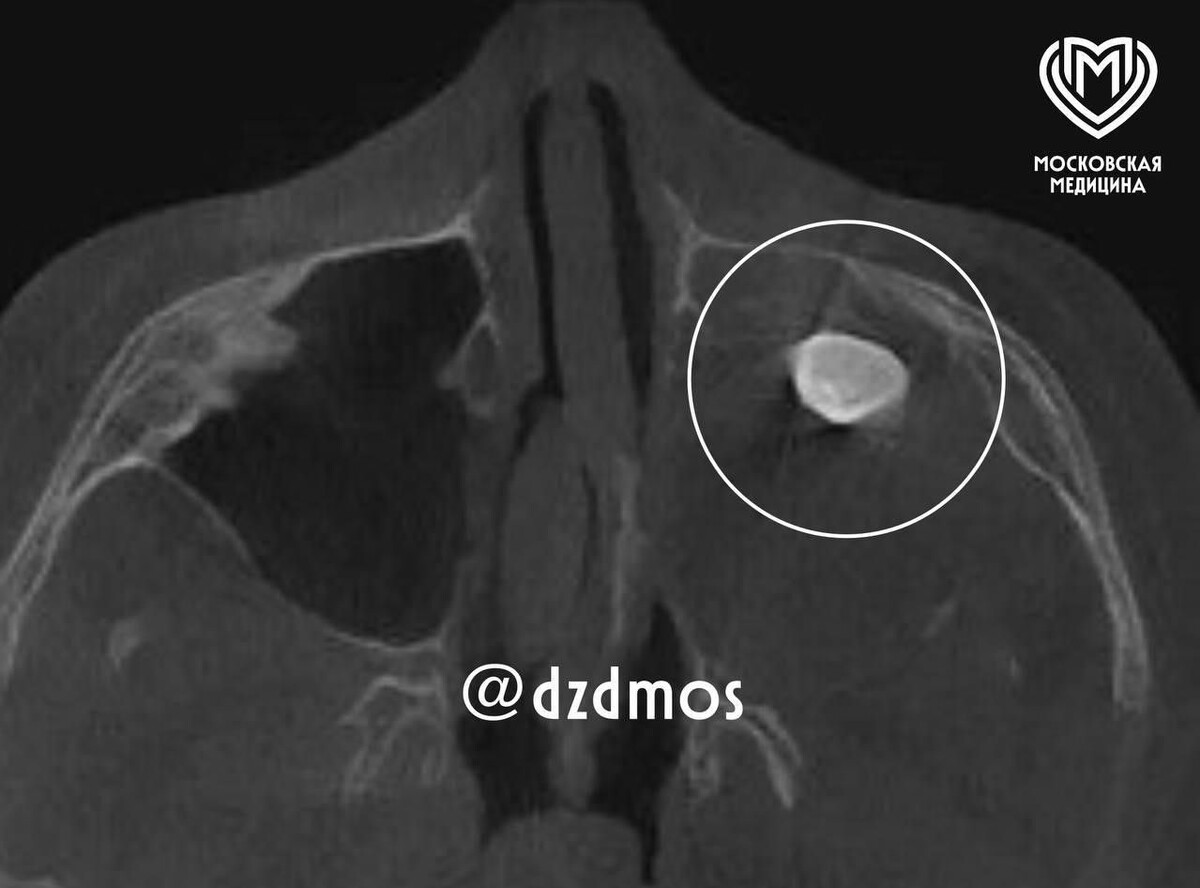

Московские врачи удалили выросший в носу у подростка зуб

Врачи Филатовской больницы удалили выросший в носу у подростка зуб. Об этом 17 марта рассказали в депздраве Москвы. По данным департамента, 15-летний подросток попал в больницу с жалобами на асимметрию лица и заложенность носа. «Мальчику нужно было провести операцию по Колдуэлу Люку, то есть обеспечить доступ через верхнюю десну, чтобы вернуть ему возможность нормально дышать. Сделав разрез, врачи обнаружили новообразование, внутри которого и находился зуб», — передали слова врачей больницы в Telegram-канале столичного депздрава. Исследования показали, что это тератома — эмбрионально-клеточное новообразование, внутри которого могут находиться элементы тканей, несвойственные этому участку тела. Врачи отметили, что тератомы очень редко встречаются в районе лица. Тератома оказалась доброкачественной. Пациента выписали после восстановления всех функций, и со временем асимметрия лица и заложенность носа полностью прошли. Ранее, 6 марта, в Орске Оренбургской области врачи удалили зуб из носа

«Мальчику нужно было провести операцию по Колдуэлу Люку, то есть обеспечить доступ через верхнюю десну, чтобы вернуть ему возможность нормально дышать. Сделав разрез, врачи обнаружили новообразование, внутри которого и находился зуб», — передали слова врачей больницы в Telegram-канале столичного депздрава.

Исследования показали, что это тератома — эмбрионально-клеточное новообразование, внутри которого могут находиться элементы тканей, несвойственные этому участку тела. Врачи отметили, что тератомы очень редко встречаются в районе лица.

Тератома оказалась доброкачественной. Пациента выписали после восстановления всех функций, и со временем асимметрия лица и заложенность носа полностью прошли.